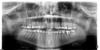

vicvil Опубликовано 14 января, 2011 Поделиться Опубликовано 14 января, 2011 Добрый день!Раз уж коснулась зубов, есть такая проблема: После того как у меня откололась пол зуба, на нижнюю восьмерку установили штифт и на него наростили зуб, но время от времени зуб воспаляется , возможно ли его вылечить или уже только удалять??? на орто вроде бы воспаление видно на орто воспаление и штифт видно на семерке!лечить нужно, удалить еще успеете! необходимо попытаться перелечить каналы. Если удастся справится с воспалением, окончательный результат лечения-вкладка и коронка. Ссылка на комментарий

x3m Опубликовано 14 января, 2011 Поделиться Опубликовано 14 января, 2011 евгешка, Вы на каком сроке беременности? по сути - сделать цифровой (не на пленку) прицельный снимок. Называется "радиовизиография".тогда можно сказать конкретней. насколько видно по обзорному снимку, зуб лечибельный.во время беременности лечить зубы лучше во второй триместр (меньше рисков). анестетики - артикаинового ряда (действ.вещество - артикаин).имхо, делать с зубом нужно УЖЕ что-то (лечить или удалять), т.к. очаг хронической инфекции вам обоим ни к чему. верно?если лечить - тогда извлечь штифт, промыть и запломбировать все каналы до самых кончиков , изготовить штифт. И на этот зуб со штифтом сделать коронку. Ссылка на комментарий